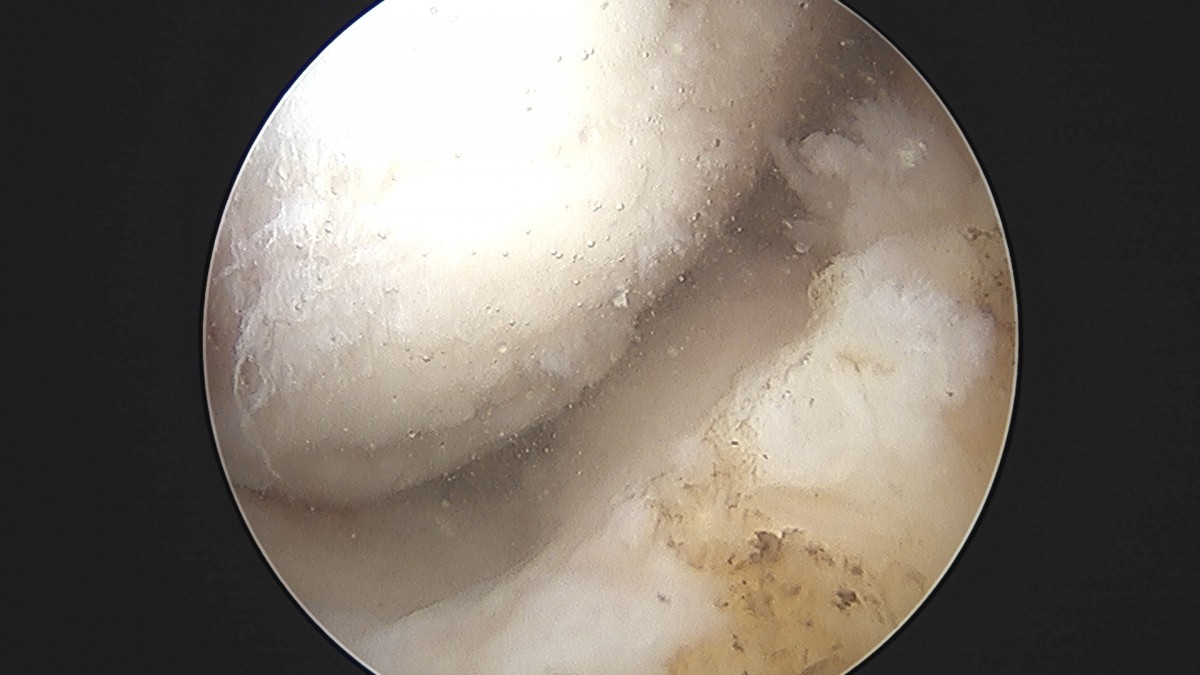

정지영원장님 무릎 반월상 연골판 절제술 이영O 환자

작성자 최고관리자 댓글 0건 조회 756회 작성일 25-09-16 16:56